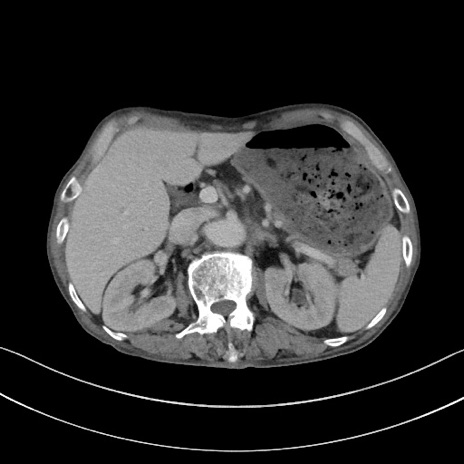

症例3(横断像)

【症例】 70歳代男性

【主訴】右鼠径部腫瘤、疼痛

【現病歴】本日朝より上記主訴あり、受診。

【既往歴】膀胱癌にて膀胱全摘、両側尿管皮膚瘻

【データ】WBC 5600、CRP 0.56